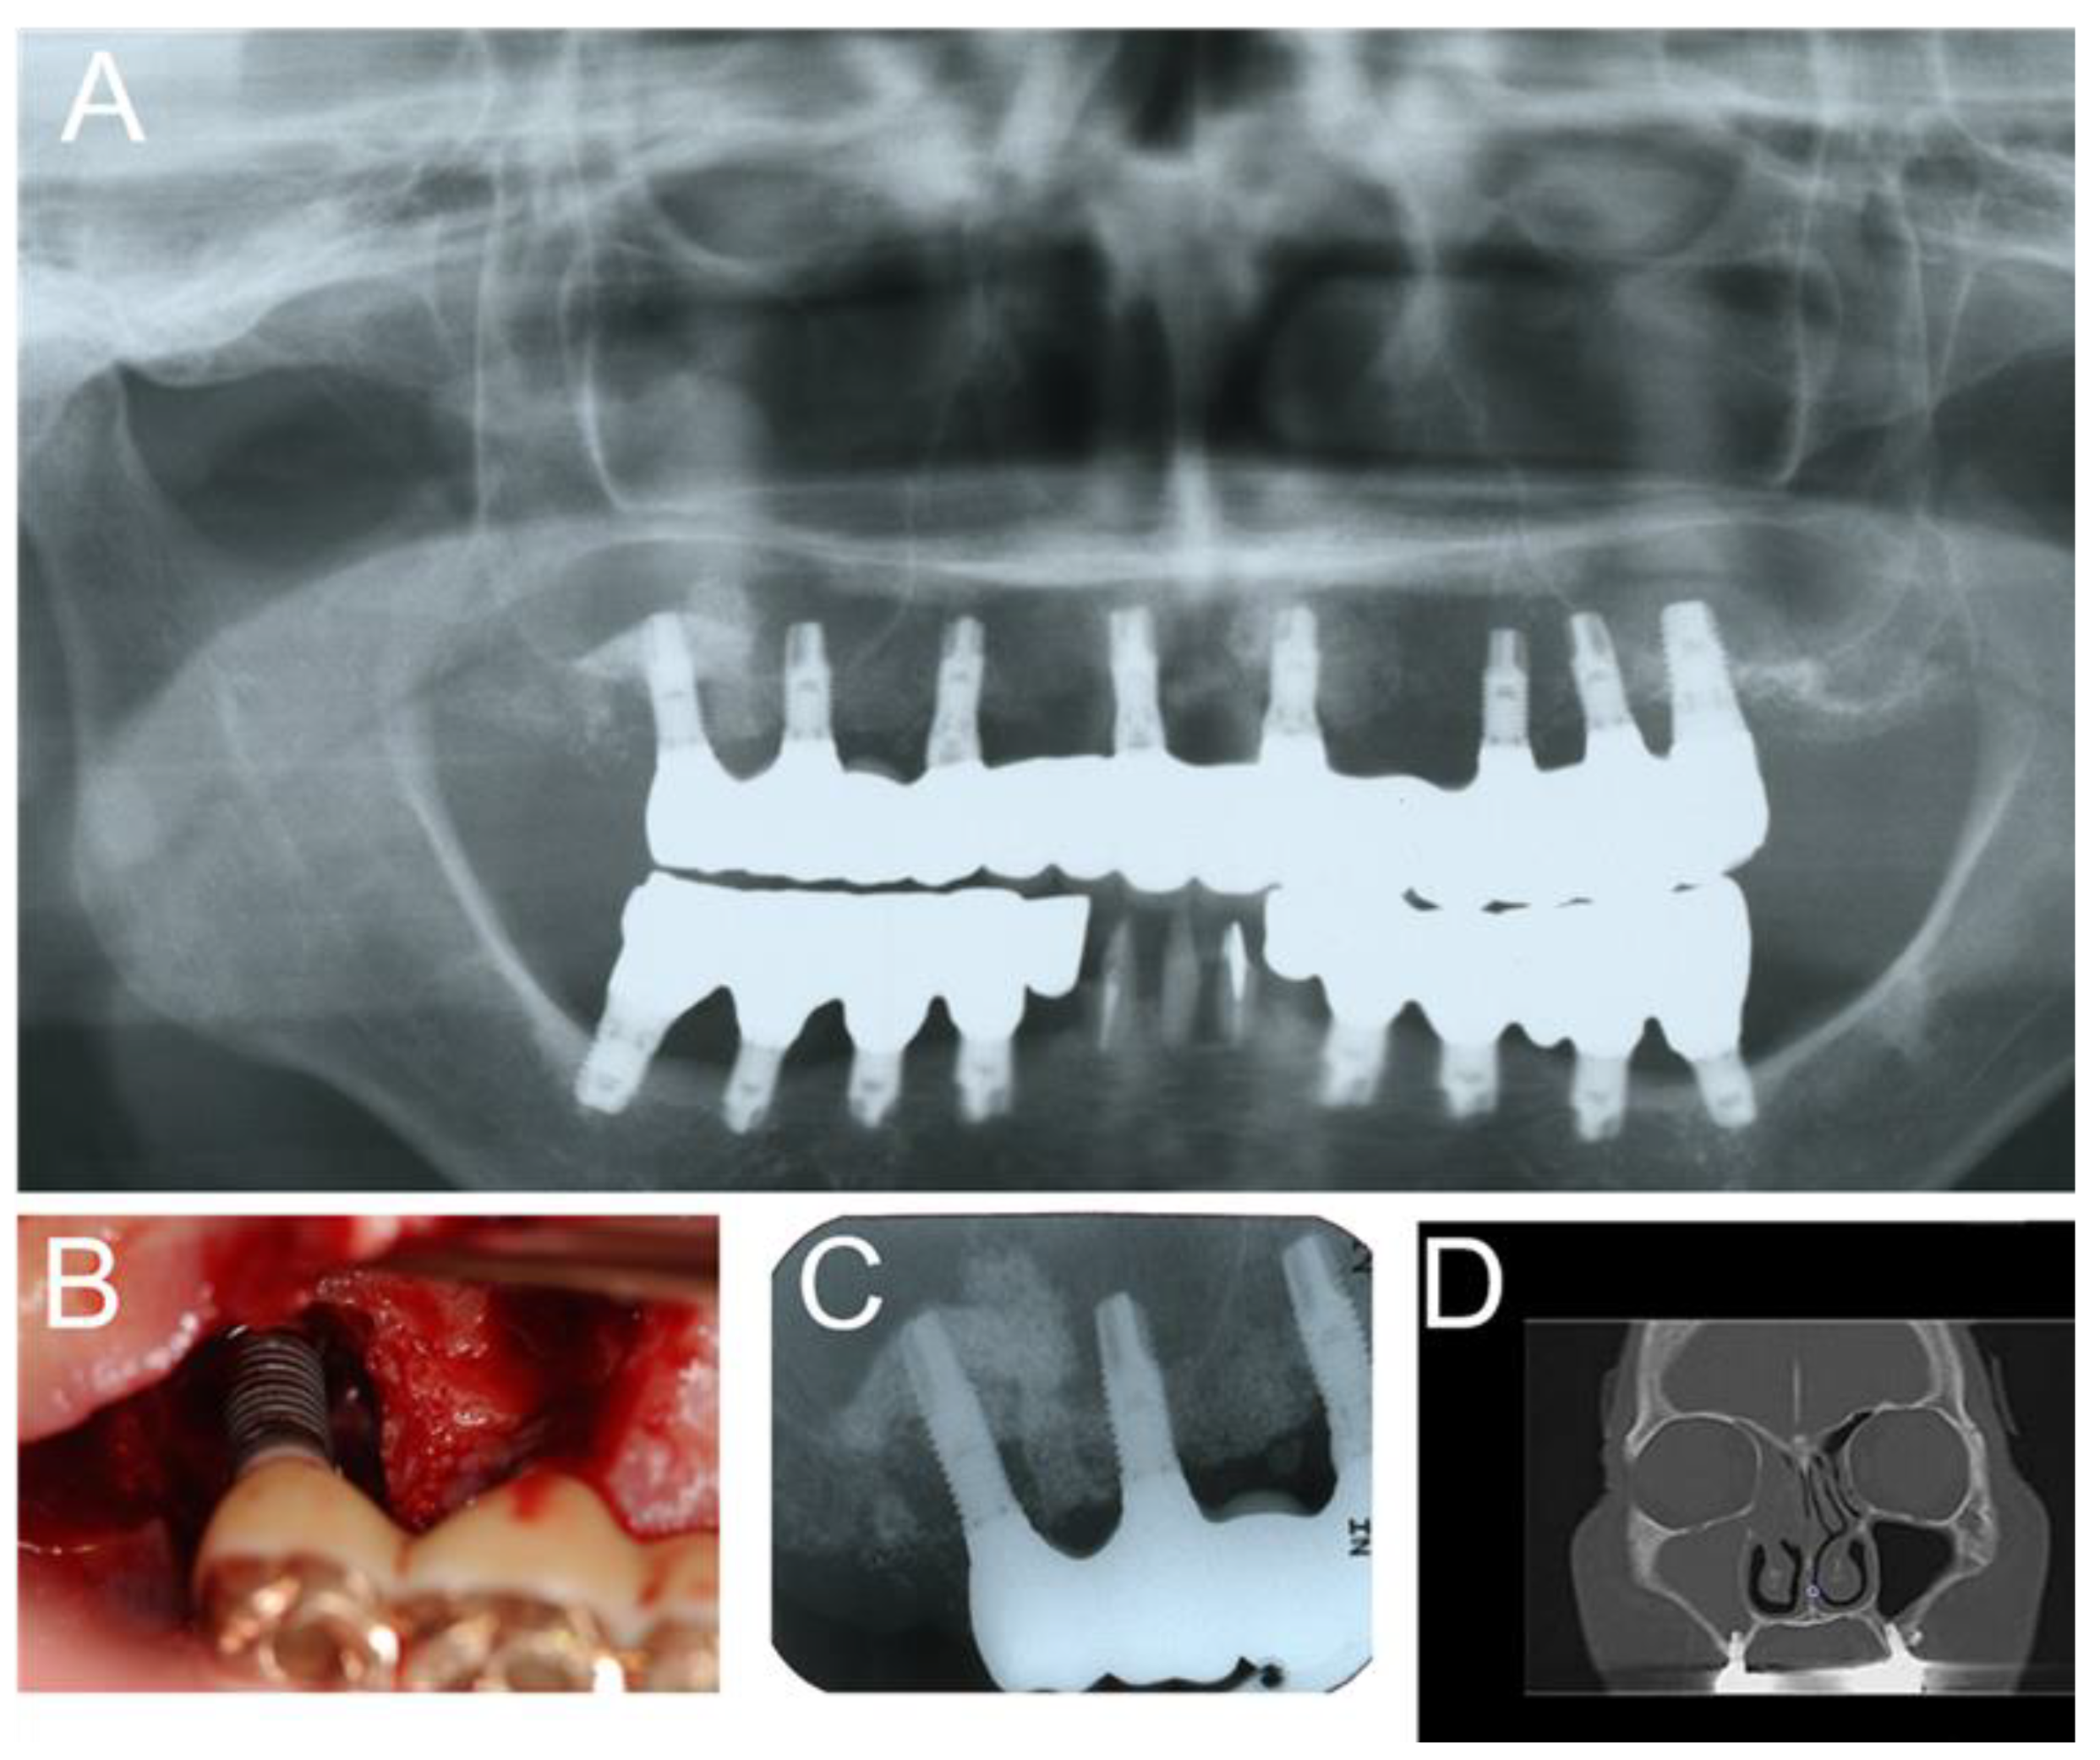

2.2. Dental Causes such as Poor Oral Hygiene, Persistent/Recurrent Periodontitis, and Peri-Implantitis

2.3. Alterations of the Anatomical Structure That Can Facilitate the Impairment of the Maxillary Sinus Drainage Pathway